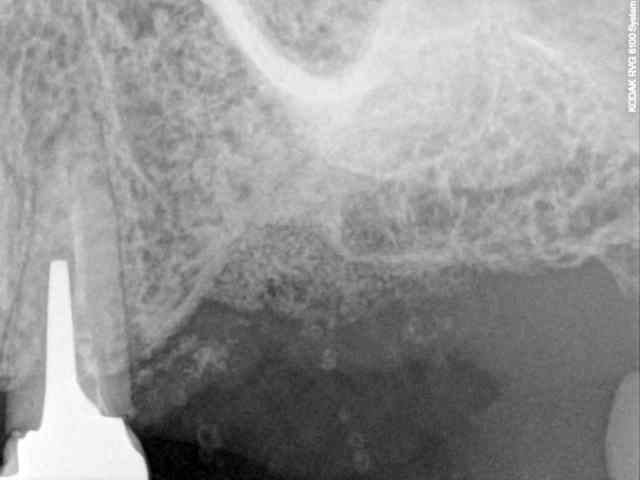

je dois pratiquer un rehaussement de plancher sinusien par volet latéral et je ne sais comment gérer le décollement de la membrane de Schneider au niveau de la communication bucco sinusale

je joins quelques captures pour vous faire une idée

Capt 1957337 h0muvi - Eugenol

Capt 1947248 ubk4pf - Eugenol

Capt 1949039 yc99fq - Eugenol

Capt 1956296 sqhfp8 - Eugenol